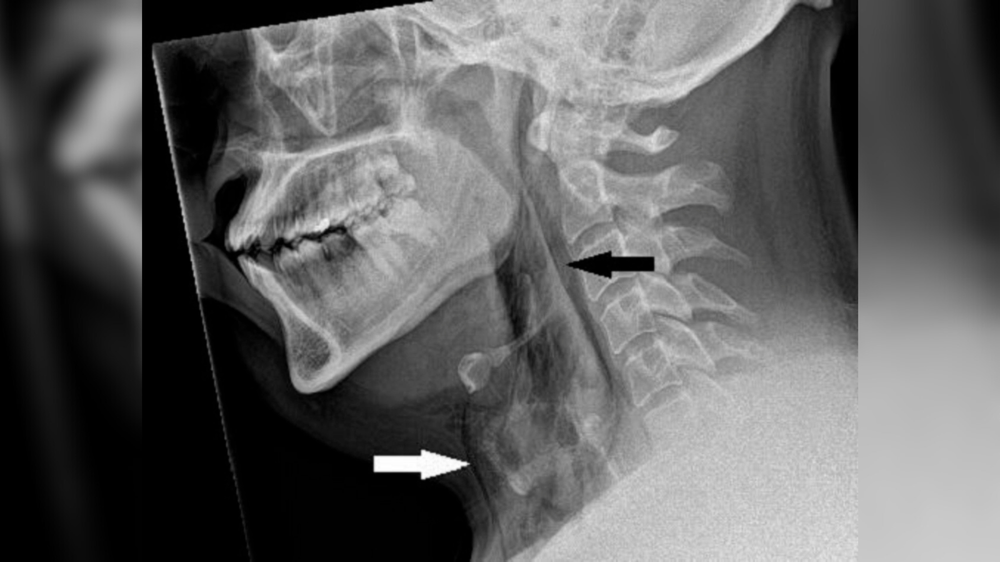

Kết quả chụp X-quang cổ cho thấy người đàn ông này bị khí phế thũng - tình trạng không khí bị mắc kẹt dưới các lớp mô sâu nhất bên dưới da.

Kết quả chụp cắt lớp vi tính (CT) sau đó cho thấy vết rách nằm giữa xương thứ ba và thứ tư, hay còn gọi là đốt sống, trên cổ của anh ta. Không khí cũng đã tích tụ trong khoảng trống giữa phổi của người này.

Các bác sĩ kết luận rằng vết rách là do "áp lực tích tụ nhanh chóng trong khí quản khi hắt hơi khi mũi bị bịt và ngậm miệng".

Trong trường hợp của người đàn ông này, do không được thoát hơi ra, áp lực tạo ra ở đường hô hấp trên lớn đến mức đã xé một lỗ có kích thước 2x2 mm trong khí quản của anh ta.